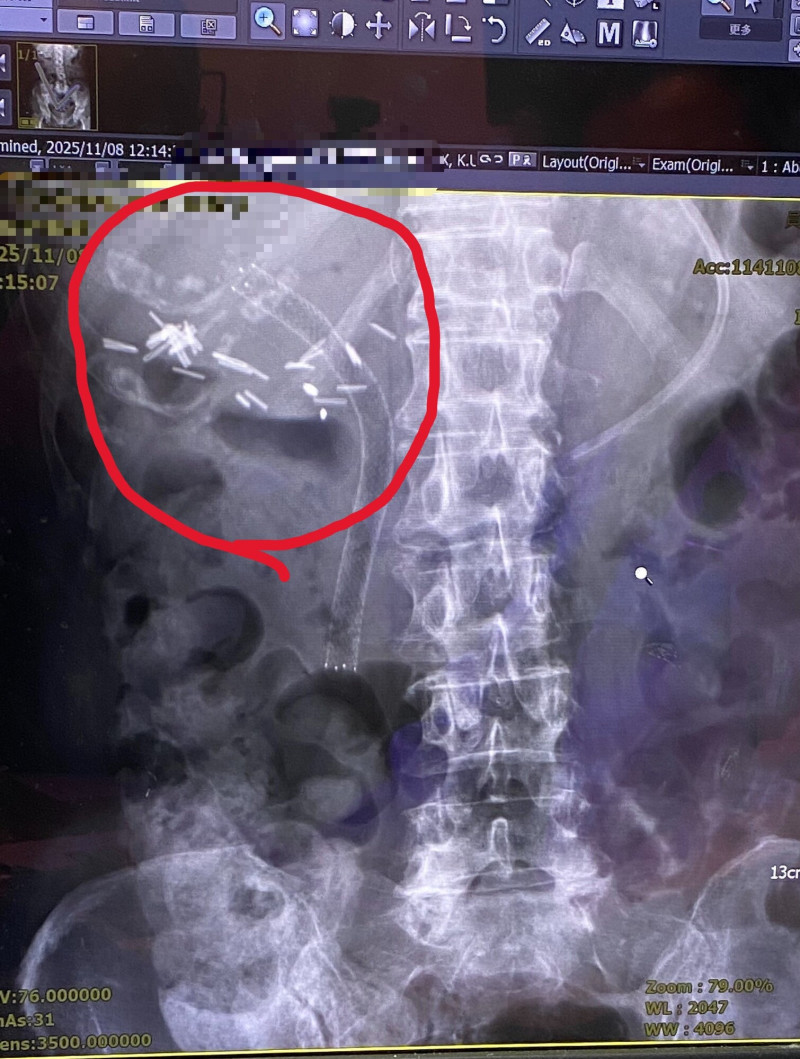

〔記者陳冠備/彰化報導〕76歲李姓婦人日前因腹痛、發燒及噁心不斷等症狀,被送往急診,檢查發現,她先前置放的「塑膠膽道支架」已完全阻塞,導致膽汁無法排出、肝功能急速惡化,面臨敗血症風險。員榮醫院醫療團隊緊急移除阻塞的支架,改置放「金屬膽道支架」,終於使膽汁恢復引流,李婦才順利脫離險境。

員榮醫院胃腸肝膽科醫師曾宇辰表示,該患者數月前因膽道腫瘤在其他醫院接受手術,術後出現膽道狹窄,於是接受「逆行性胰膽管鏡(ERCP)」手術,並置放塑膠支架。

然而近日因腹痛、發燒加劇送醫,檢查發現其黃疸與膽道指數明顯上升,確認是塑膠支架完全阻塞所致。經醫療團隊討論,考量患者屬惡性腫瘤適應症,建議將塑膠支架更換為金屬支架,以改善引流並降低再次阻塞風險。術後,患者恢復良好,目前於門診定期追蹤,未再出現黃疸、腹痛或感染情形。